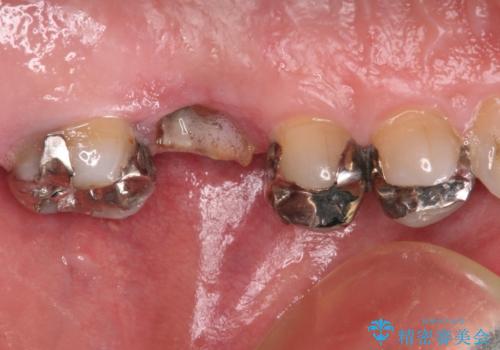

- 根っこの一部だけになった歯と咬むと痛みのある歯を気にして来院された患者様です。

上顎の歯根のみとなった歯は抜歯が必要であったので、抜歯を行い、インプラントあるいはブリッジのよる補綴治療を提案しました。

前後の歯は銀歯が装着されていたため、ブリッジによる補綴治療として、前後の歯もセラミックに置き換えることとしました。

下顎の根管治療がされた大臼歯は咬合時に痛みが認められたため、再度根管治療を行った後に補綴治療することとしました。